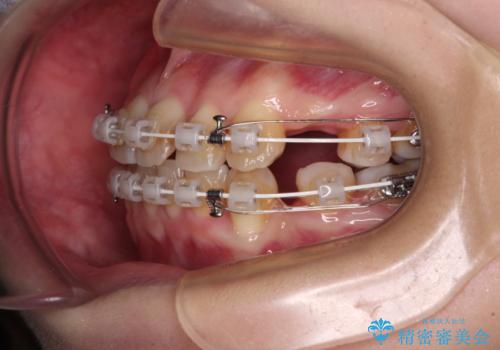

- 矯正装置

- 審美装置

- 上下の八重歯と前歯のデコボコを気にして来院された患者様です。

右上と左下の八重歯が特に著しく、上顎正中が右側にシフトしていました。

デコボコが強いため小臼歯4本を抜歯し、上顎正中を左側に移動させるために補助装置を使用して、ワイヤー装置にて矯正治療を行うこととしました。

八重歯のためずれていた上下の正中をほぼ一致する位置に整えることができました。